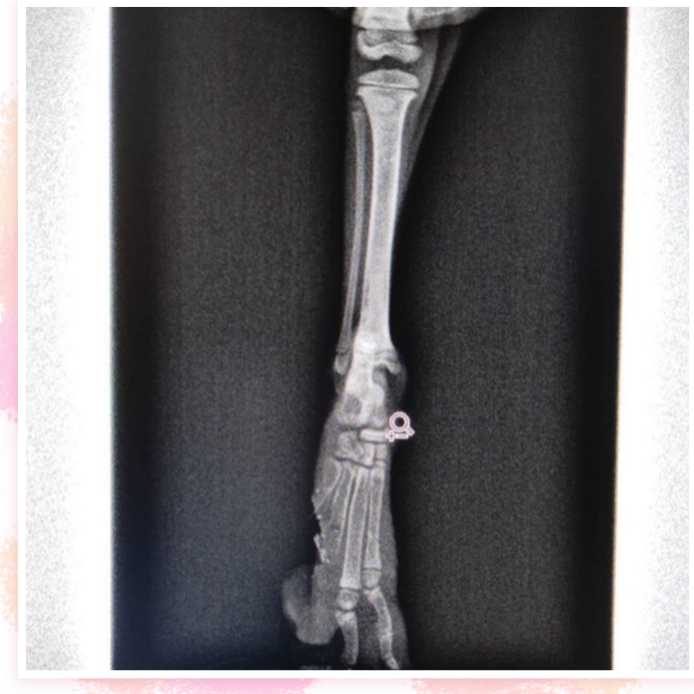

昨日、沖縄から負傷猫ちゃんの保護依頼が来ました。

まだ430gのちいちゃい子です( ; ›ω‹ )

遺棄されていたそうです。。

なんと肉球がパックリ2個切れてるそう。。

ボンネットに入ってか?何かに挟まれてかの事故

にあったのか?幸い骨折などはなく歩けるようです。

これから毎日消毒洗浄して、お薬を塗って

回復を待ちます。

飛行機に乗れるようになったらこちらに来れます。